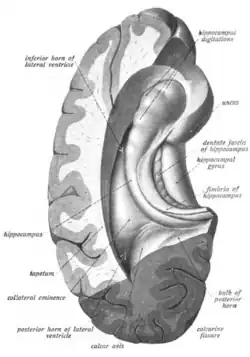

The hippocampus is a five centimeter long ridge of gray matter tissue within the parahippocampal gyrus that can only be seen when the gyrus is opened.[15][16] The hippocampus is an inward fold of three-layered archicortex (one of three regions of the allocortex) into the medial temporal lobe of the brain, where it elevates into the floor of each lateral ventricle inferior horn.[17][18][19][20] The hippocampus stretches along its anterior-posterior axis, from the amygdala to the splenium of the corpus callosum, with the head, body, and tail regions as subdivisions of this axis.[21][15] The dentate gyrus, CA subfields, fimbria, and subiculum are divisions across the short axis, the proximal-distal axis.[21]

The hippocampus, and dentate gyrus that is folded into the hippocampal archicortex have the shape of a curved, rolled-up tube. The curve of the hippocampus (known as cornu Ammonis) uses the initial letters CA to name the hippocampal subfields CA1-CA4. CA4 is in fact the polymorphic layer or hilus of the dentate gyrus, but CA4 is still sometimes in use to describe the part of CA3 that inserts between the dentate gyrus regions or blades.[17][27]

It can be distinguished as an area where the cortex narrows into a single layer of densely packed pyramidal neurons, which curl into a tight U shape. One edge of the "U" is CA4, the hilus of the dentate gyrus. This is embedded into the backward-facing, flexed dentate gyrus. In humans the hippocampus is described as having an anterior and posterior part; in other primates they are termed rostral and caudal, and in rodent literature they are the ventral and dorsal part.[28] Both parts are of similar composition but belong to different neural circuits.[29] The dentate gyrus combined with other hippocampal regions form a banana-like structure, with the two hippocampi joined at the stems by the commissure of fornix (also called the hippocampal commissure).[19][30] In primates, the part of the hippocampus at the bottom, near the base of the temporal lobe, is much broader than the part at the top. This means that in cross-section the hippocampus can show a number of different shapes, depending on the angle and location of the cut.[31]